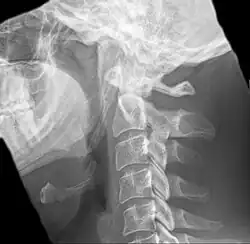

-

Radiograph, lateral view showing elongated stylohyoid process and stylohyoid ligament ossification -

Radiograph, lateral view showing joint-like formation in ossified stylohyoid ligament -

Imaging is important and is diagnostic. Visualizing the styloid process on a CT scan with 3D reconstruction is the suggested imaging technique.[13] The enlarged styloid may be visible on an orthopantogram or a lateral soft tissue X ray of the neck.